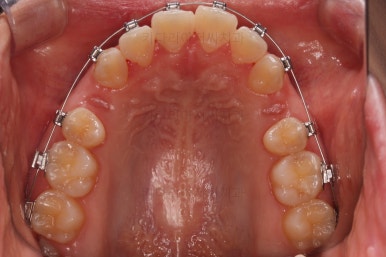

점점 이 뽑은 자리가 줄어가네요.

이 쯤 됨녀 중간평가를 해줘요.

자연스레 자리를 없애고 마무리를 할 것인지, 그것 보다 훨씬 더 많이 넣어볼 것인지, 아니면 오히려 앞으로 뺄지 말이죠.

처음보다 입매도 많이 좋아졌지만 환자분은 기왕 하는김에 되는데까지 맥시멈으로 많이 입을 넣어보고 싶다고 하시더라고요.

원하시는 목표량은 이 뽑은 자리로 앞니를 다 넣어도 안될 듯 하여 추가로 사랑니 발치를 하고 미니스크류를 이용해서 더 넣어보기로 했어요.

위아래 좌우 모두 사랑니도 발치를 하고 네 군데 모두 미니스크류를 하여 최대한 당겨보기로 하였습니다.